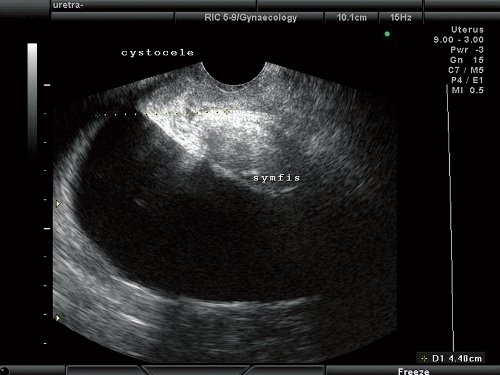

У всех 350 пациенток с цистоцеле выявлено смещение задней стенки мочевого пузыря ниже нижнего края лона, в 201 (57,4%) случае - при натуживании, в 149 (42,6%) - в покое и при пробе Вальсальвы. Из представленных данных видно, что наиболее значимыми эхографическими признаками цистоцеле служат смещение задней стенки мочевого пузыря на уровень нижнего края лона и ниже при натуживании. Для цистоцеле без дефекта фасции характерна картина гипермобильности уретро-везикального сегмента (рис. 3).

Рис. 3. Цистоцеле без дефекта пубо-цервикальной фасции. Смещение задней стенки мочевого пузыря ниже уровня нижнего края лона.